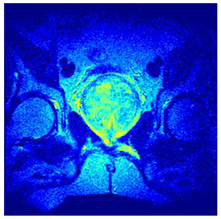

| Image | nt = 3 | nt = 4 | nt = 5 | nt = 8 |

|---|---|---|---|---|

| 1 | ![]() | ![]() | ![]() | ![]() |

| 2 | ![]() | ![]() | ![]() | ![]() |

| 3 | ![]() | ![]() | ![]() | ![]() |

| 4 | ![]() | ![]() | ![]() | ![]() |

| 5 | ![]() | ![]() | ![]() | ![]() |

| 6 | ![]() | ![]() | ![]() | ![]() |

| 7 | ![]() | ![]() | ![]() | ![]() |

| 8 | ![]() | ![]() | ![]() | ![]() |

| 9 | ![]() | ![]() | ![]() | ![]() |

| 10 | ![]() | ![]() | ![]() | ![]() |

| 11 | ![]() | ![]() | ![]() | ![]() |